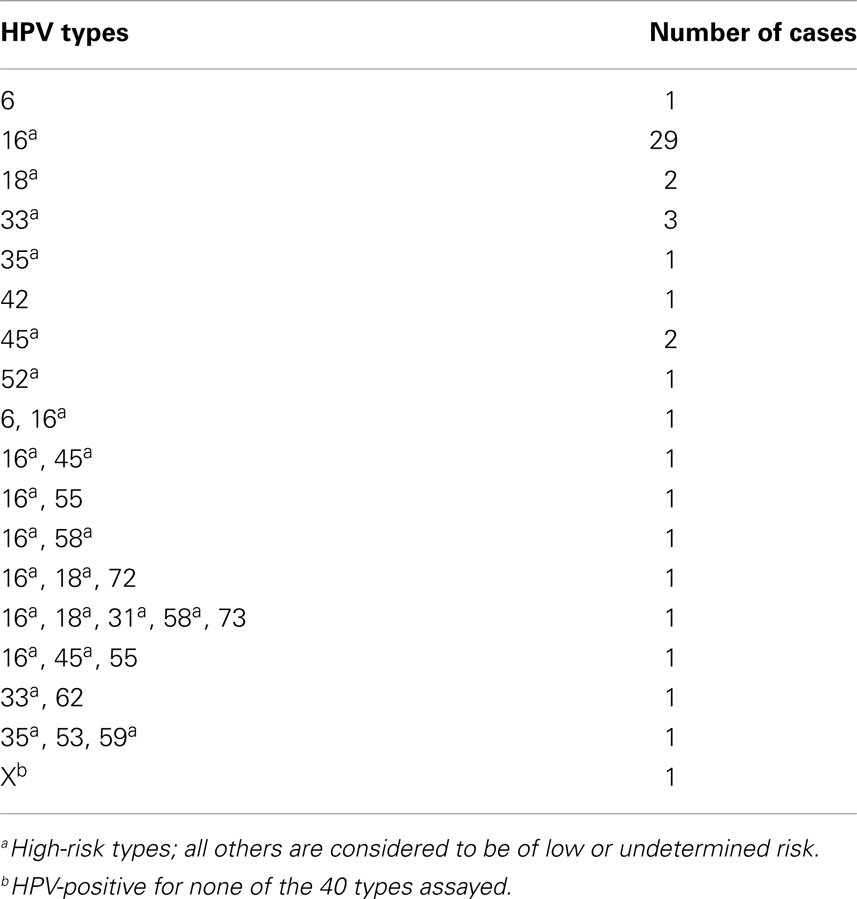

penile cancer photos download

Posts: penile cancer photos download